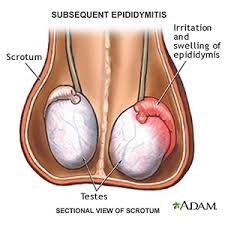

ΕΠΙΔΙΔΥΜΙΤΙΔΑ – ΟΞΕΙΑ ΟΡΧΕΟΕΠΙΔΙΔΥΜΙΤΙΔΑ

Ο αποικισμός της επιδιδυμίδας ( ενός οργάνου που καλύπτει το πάνω μέρος του όρχη και συνδέει τον όρχη με το σπερματικό πόρο το σωλήνα δηλαδή που μεταφέρει τα σπερματοζωάρια) από μικρόβια συνήθως Gram αρνητικά όπως e-coli, εντερόκοκκος, και σπανιότερα ουρεάπλασμα, μυκόπλασμα και χλαμύδια. Η μεταφορά του μικροβίου έχει τον ίδιο μηχανισμό με την οξεία προστατίτιδα (σεξουαλική επαφή–αποφρακτική ροή) που όμως αντί το μικρόβιο να δημιουργήσει φλεγμονή στον προστάτη εγκαθίστανται στην επιδιδυμίδα με συμμετοχή ή όχι του όρχεος (ορχεοεπιδιδυμίτιδα).

Ποια τα συμπτώματα της επιδιδυμίτιδας;

- αίσθημα βάρους και έντονης ευαισθησίας στο ημιόσχεο που πάσχει ειδικά κατά την ψηλάφιση και κατά το περπάτημα

- πυρετός ως 39-40ο C, ρίγος

- έντονο άλγος ως και τη σύστοιχη βουβωνική χώρα

- διόγκωση και πιθανή ερυθρότητα στο δέρμα του οσχέου

- δυσουρία, συχνοουρία

- πόνος κατά την εκσπερμάτιση

- αίσθημα καταβολής

- έντονος πονοκέφαλος

Η διάγνωση γίνεται με την κλινική εξέταση και με εξετάσεις αίματος CRP και ΤΚΕ (αποτελούν δείκτες φλεγμονής) γενική και καλλιέργεια ούρων που συνήθως αναδεικνύουν τον αιτιολογικό παράγοντα και υπερηχογράφημα οσχέου σε συνδυασμό με έγχρωμο Doppler –triplex όρχεων ο οποίος θα αποδείξει τη διόγκωση της επιδιδυμίδας καθώς και την έντονη υπεραιμία και θα παρέχει πληροφορίες για μια άλλη σοβαρή κατάσταση με παρόμοια συμπτώματα που απαιτεί επείγουσα χειρουργική επέμβαση που ονομάζεται συστροφή όρχεος.

Η θεραπεία γίνεται με αντιβιοτικά από του στόματος ή και ενέσιμα, με αντιφλεγμονώδη για τη μείωση του οιδήματος και του πόνου. Σημαντικός παράγοντας είναι η θέση των όρχεων να είναι υψηλή και οι όρχεις να μην κρέμονται από το βάρος τους (χρήση ειδικών σπασουάρ). Μετά τη θεραπεία η σκληρία στην επιδιδυμίδα και η διόγκωσή της με απουσία του πόνου μπορεί να παραμείνει μέχρι και ως ένα τρίμηνο.

Επιπλοκές

- συλλογή υγρού γύρω από τον όρχη

- δημιουργία αποστήματος στην επιδιδυμίδα (συλλογή πύου η οποία μπορεί να χρειαστεί χειρουργική παροχέτευση)

- μικρή πιθανότητα εμφάνισης υπογονιμότητας (η επιδιδυμίδα είναι το σημείο της ωρίμανσης των σπερματοζωαρίων όπου τα σπερματοζωάρια αποκτούν ικανότητα για γονιμοποίηση).